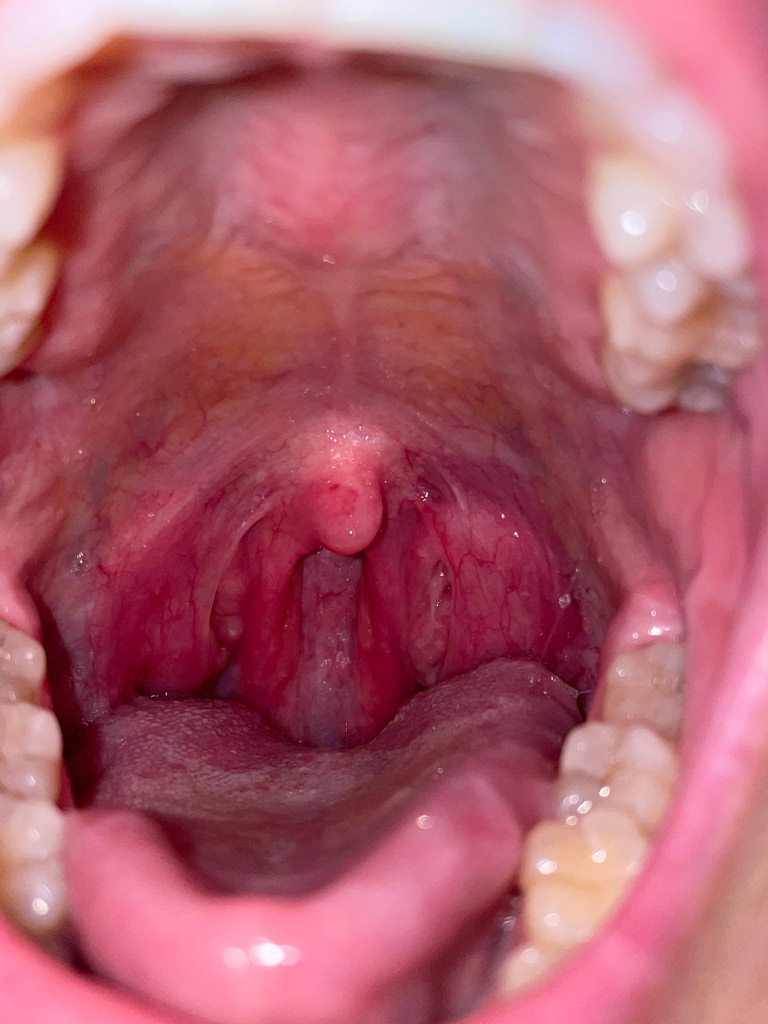

GRAPHIC… Super weird swelling in my throat (all tests continually came back negative)